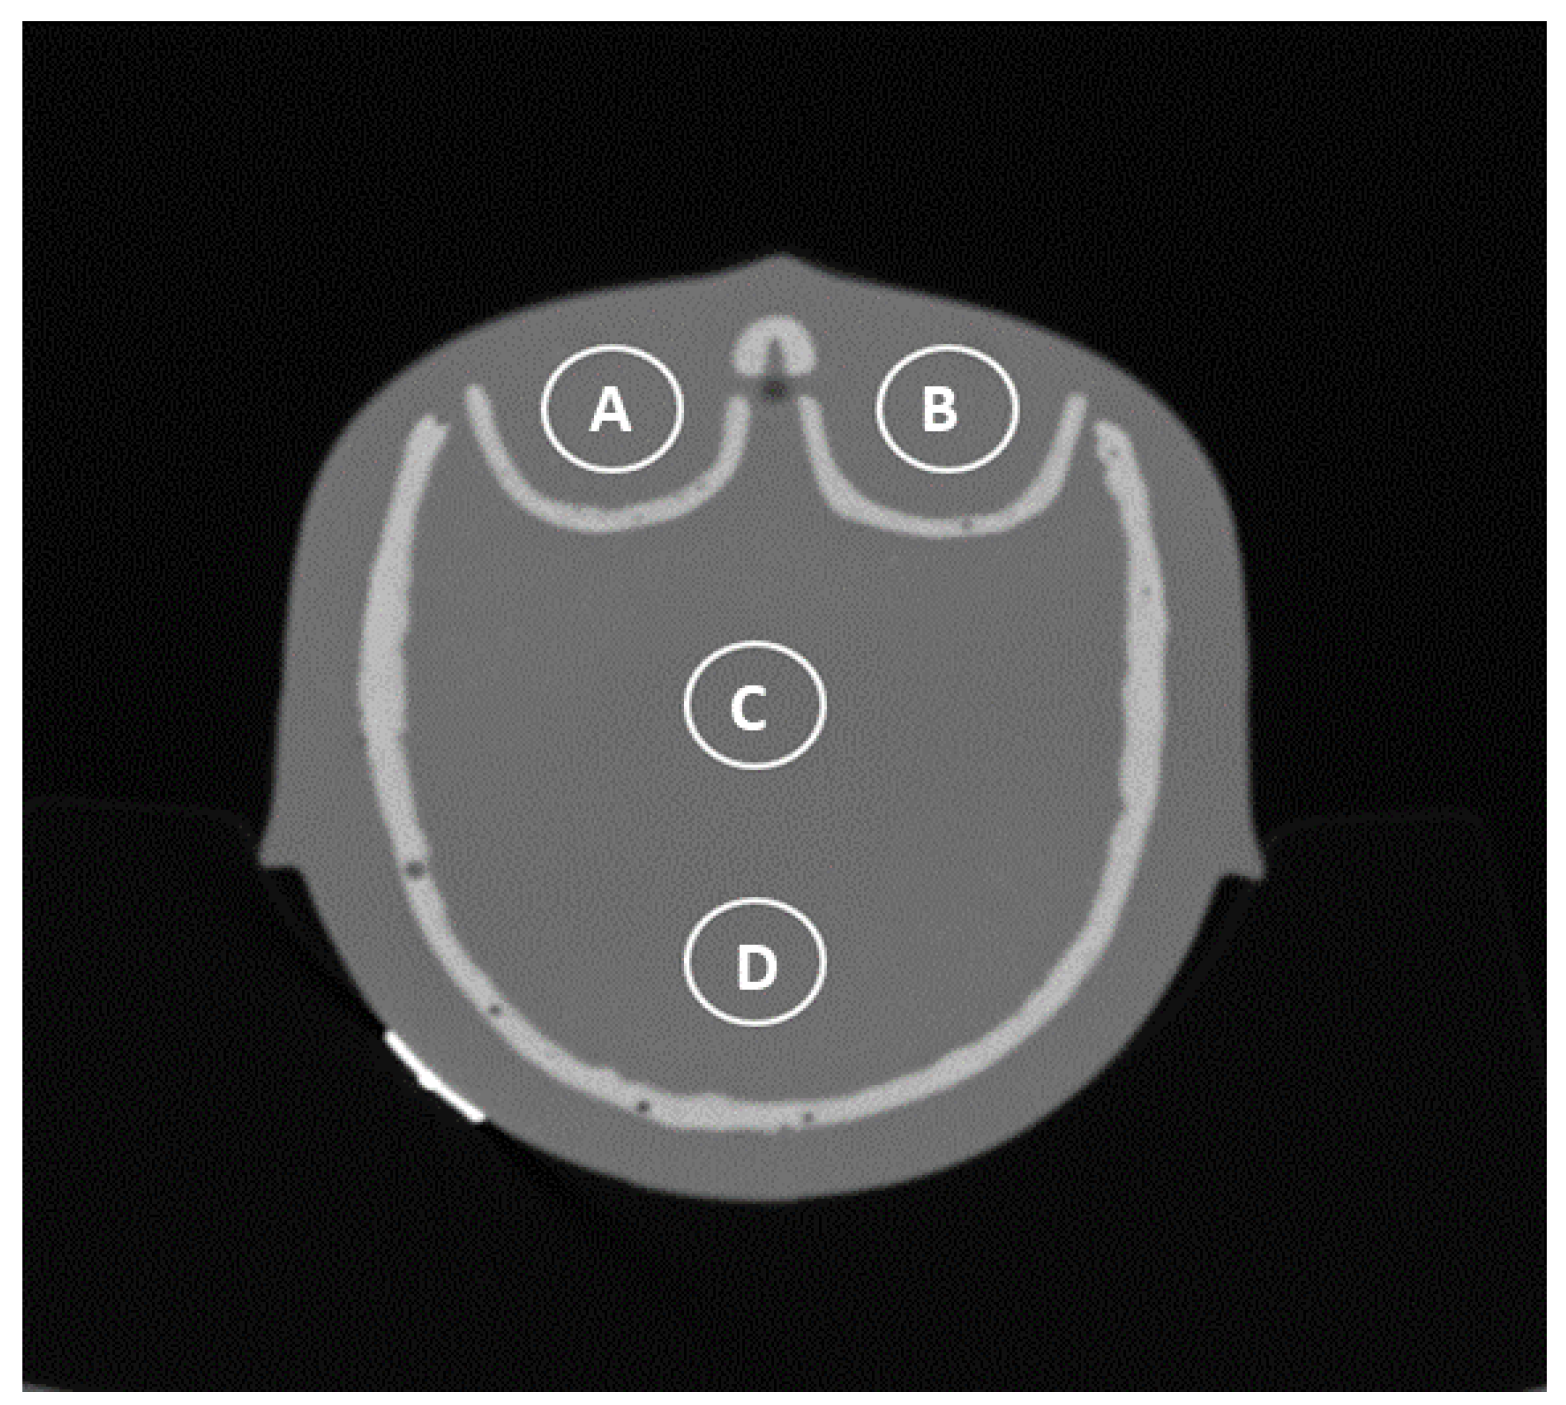

Image noise was estimated using the standard deviation of density values (Hounsfield units, HU) within a circular region of interest (ROI—Figure 3) and served as a quantitative parameter of image quality.

Figure 3.

Different points of ROI measurement: orbital right (A), orbital left (B), central in the cranium (C), and occiput (D).